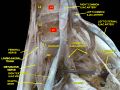

العجز، السطح الحوضي. | |